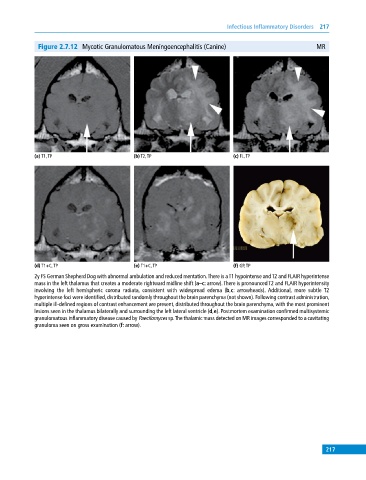

Figure 2.7.12 Mycotic Granulomatous Meningoencephalitis (Canine) MR

(a) T1, TP (b) T2, TP (c) FL, TP

(d) T1+C, TP (e) T1+C, TP (f) GP, TP

2y FS German Shepherd Dog with abnormal ambulation and reduced mentation. There is a T1 hypointense and T2 and FLAIR hyperintense

mass in the left thalamus that creates a moderate rightward midline shift (a–c: arrow). There is pronounced T2 and FLAIR hyperintensity

involving the left hemispheric corona radiata, consistent with widespread edema (b,c: arrowheads). Additional, more subtle T2

hyperintense foci were identified, distributed randomly throughout the brain parenchyma (not shown). Following contrast administration,

multiple ill‐defined regions of contrast enhancement are present, distributed throughout the brain parenchyma, with the most prominent

lesions seen in the thalamus bilaterally and surrounding the left lateral ventricle (d,e). Postmortem examination confirmed multisystemic

granulomatous inflammatory disease caused by Paecilomyces sp. The thalamic mass detected on MR images corresponded to a cavitating

granuloma seen on gross examination (f: arrow).